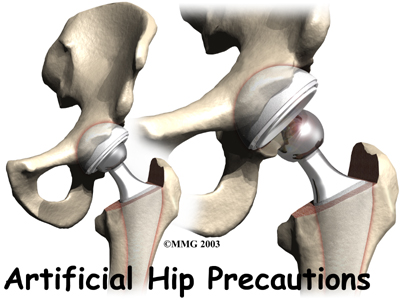

Hip surgeries such as total joint replacement and hemiarthroplasty require the surgeon to open the hip joint capsule. This puts the hip at risk of dislocating after surgery. Patients follow special precautions after surgery about which hip positions and movements need to be avoided to keep the hip from dislocating. While you are in the hospital, your health care team will remind you often about the need to follow these hip precautions. Once you get home, you will have to remember to follow these rules until your surgeon approves motion beyond these limits of movement.

The hip socket is called the acetabulum and forms a deep cup that surrounds the ball of the upper thighbone, called the femoral head. The ball and socket is surrounded by a soft-tissue enclosure called the joint capsule.

When the surgeon opens the hip joint capsule on the front edge, the procedure is called an anterior approach. Opening the joint from the back part of the joint is called a posterior approach.

Opening the Hip Joint

The joint capsule and ligaments keep the ball joint centered in the hip. When these soft tissues are cut during hip surgery, there is a greater risk for the ball to be forced out of the socket and dislocated after surgery while the soft tissues of the hip heal. The hip precautions you'll learn are used to keep your hip in safe positions. To do this, you need to avoid certain movements and positions. In this way, the ball will be less likely to push against the healing tissues and be forced out of the socket. Most surgeons prefer to have you use these precautions for at least six to twelve weeks after surgery until the healing tissues gain strength.